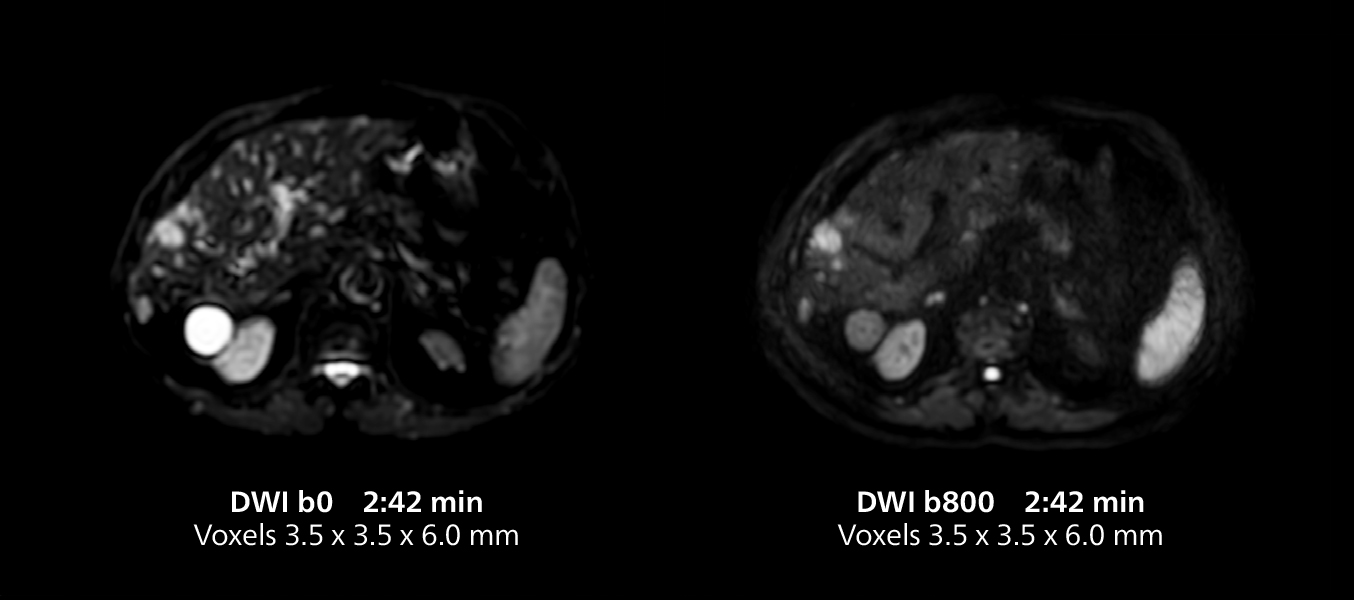

Female pelvis imaging

This MRI case illustrates good resolution and imaging quality obtained within reasonable scan times using the MR 5300 1.5T system with the anterior torso cardiac coil that allows use of a large field of view (FOV).

Female pelvis imaging

This MRI case illustrates good resolution and imaging quality obtained within reasonable scan times using the MR 5300 1.5T system with the anterior torso cardiac coil that allows use of a large field of view (FOV).

Free-breathing scans provide reproducibility and patient comfort

Dr. Gellée highlights the robust free-breathing scans as “the feature that makes the biggest difference in my daily work. The 3D free breathing sequences are very reproducible, and the axial acquisition is very good. For example, in endometriosis, which is one of my focus areas, it provides high contrast and good resolution so that I can see small details. We also use free breathing for liver and pancreas imaging. In multi-phase liver studies, 4D Free Breathing delivers 3-second temporal resolution, making a dynamic scan with more than one arterial phase possible.”

The MR 5300 with Compressed SENSE is up to 50%** faster for many exams. It can provide routine exams in less than 5 minutes and whole-body exams in less than 20 minutes. Saint-Augustin has taken advantage of that speed to create highly efficient protocols. The hospital’s standard stroke protocol is just about 8 minutes, and standard ENT, prostate PIRADS staging, and endometriosis studies all clock in at just about 10 minutes.***

“We have more speed in 3D sequences,” Dr. Gellée states. “With Compressed SENSE, we can replace two or three 2D scans withone high-quality 3D scan. High quality additional orientations are then obtained by post-processing of the 3D data set, thus saving scanning time.”